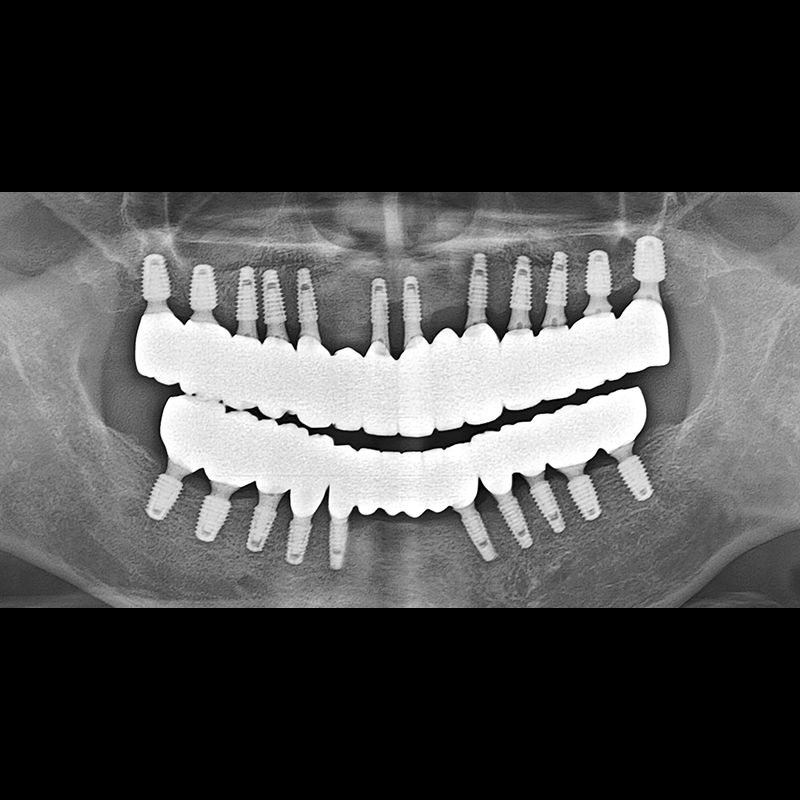

インプラント手術事例 2025.05.30

欠損した歯の部分と、生かしにくい歯の位置にインプラントを植立しました。